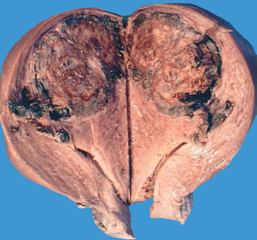

(1)肉眼观,癌结节呈单个或多个,位于子宫的不同部位,大者可突入宫腔,常侵入深肌层,甚而穿透宫壁达浆膜外。由于明显出血坏死,癌结节质软,色暗红或紫兰色。

(2)镜下,瘤组织由分化不良的细胞滋养层和合体细胞滋养层两种瘤细胞组成,细胞异型性明显,核分裂像易见。两种细胞混合排列成巢状或条索状,偶见个别癌巢主要由一种细胞组成。肿瘤自身无间质血管,依靠侵袭宿主血管获取营养,故癌组织和周围正常组织有明显出血坏死,有时癌细胞大多坏死,仅在边缘部查见少数残存的癌细胞。癌细胞不形成绒毛和水泡状结构,这一点和侵蚀性葡萄胎明显不同。

患者消瘦贫血状,腹腔内有血性液体约400mL,双侧胸腔中也有同样性状液体100mL。心脏重320g,脾脏重160g,肝脏重3200g,表面和切面见数个直径 1~2.5 cm的出血性结节,有融合。肺切面查见多个结节,直径 2cm 左右,伴出血、坏死;左右两侧肾脏各120g;脑重1300g,表面有多个出血性病灶,直径1.5cm,脑组织水肿。子宫13cm×12cm×13.5cm,子宫底后壁见直径4.5cm的出血性结节,质脆而软,切面呈紫红色,坏死、溃烂,边界不清,浸润子宫肌层并穿破肌层达浆膜,子宫旁有多个蚕豆大小的紫红色结节,双附件正常。阴道壁查见3个紫红色结节,在盆腔内也有不规则的出血性肿块。